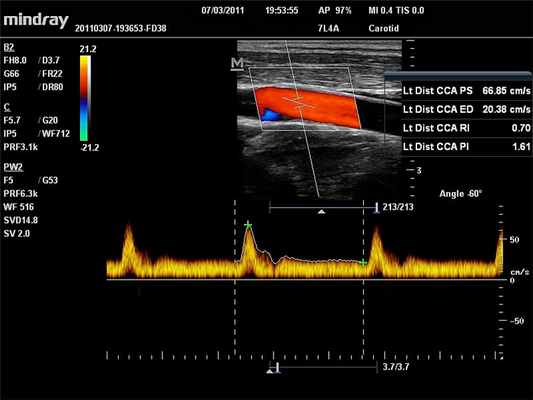

PW – режим импульсно-волнового допплера

Режим импульсно волнового допплера (pulse wave Dopper – PW) – режим, работая в котором мы пытаемся избавится от главного недостатка режима CW, а именно отсутствия пространственного разрешения (разрешающей способности по глубине). Импульсные сигналы (короткие по времени) позволяют оценить отдельные зоны по глубине, поэтому в процессе работы на ультразвуковом приборе нам необходимо выбрать зону интереса (окно опроса). Конечно же и здесь не обошлось без недостатков – главным недостатком использования режима импульсно-волнового допплера является строгое ограничение по измерению больших скоростей на больших глубинах сканирования.

CFM (CDI, CDV, CD, CF, ЦДК и т.д.) – режим цветового допплеровского картирования по скорости

В режиме цветового допплеровского картирования по скорости (ЦДК) изображение строится также как и в B-режиме. Отличительной особенностью режима ЦДК является цветовое отображение информации о скорости и направлении движения структур в выделенной пользователем области (окно опроса). Режим ЦДК обладает ярко выраженной зависимостью от величины допплеровского угла.